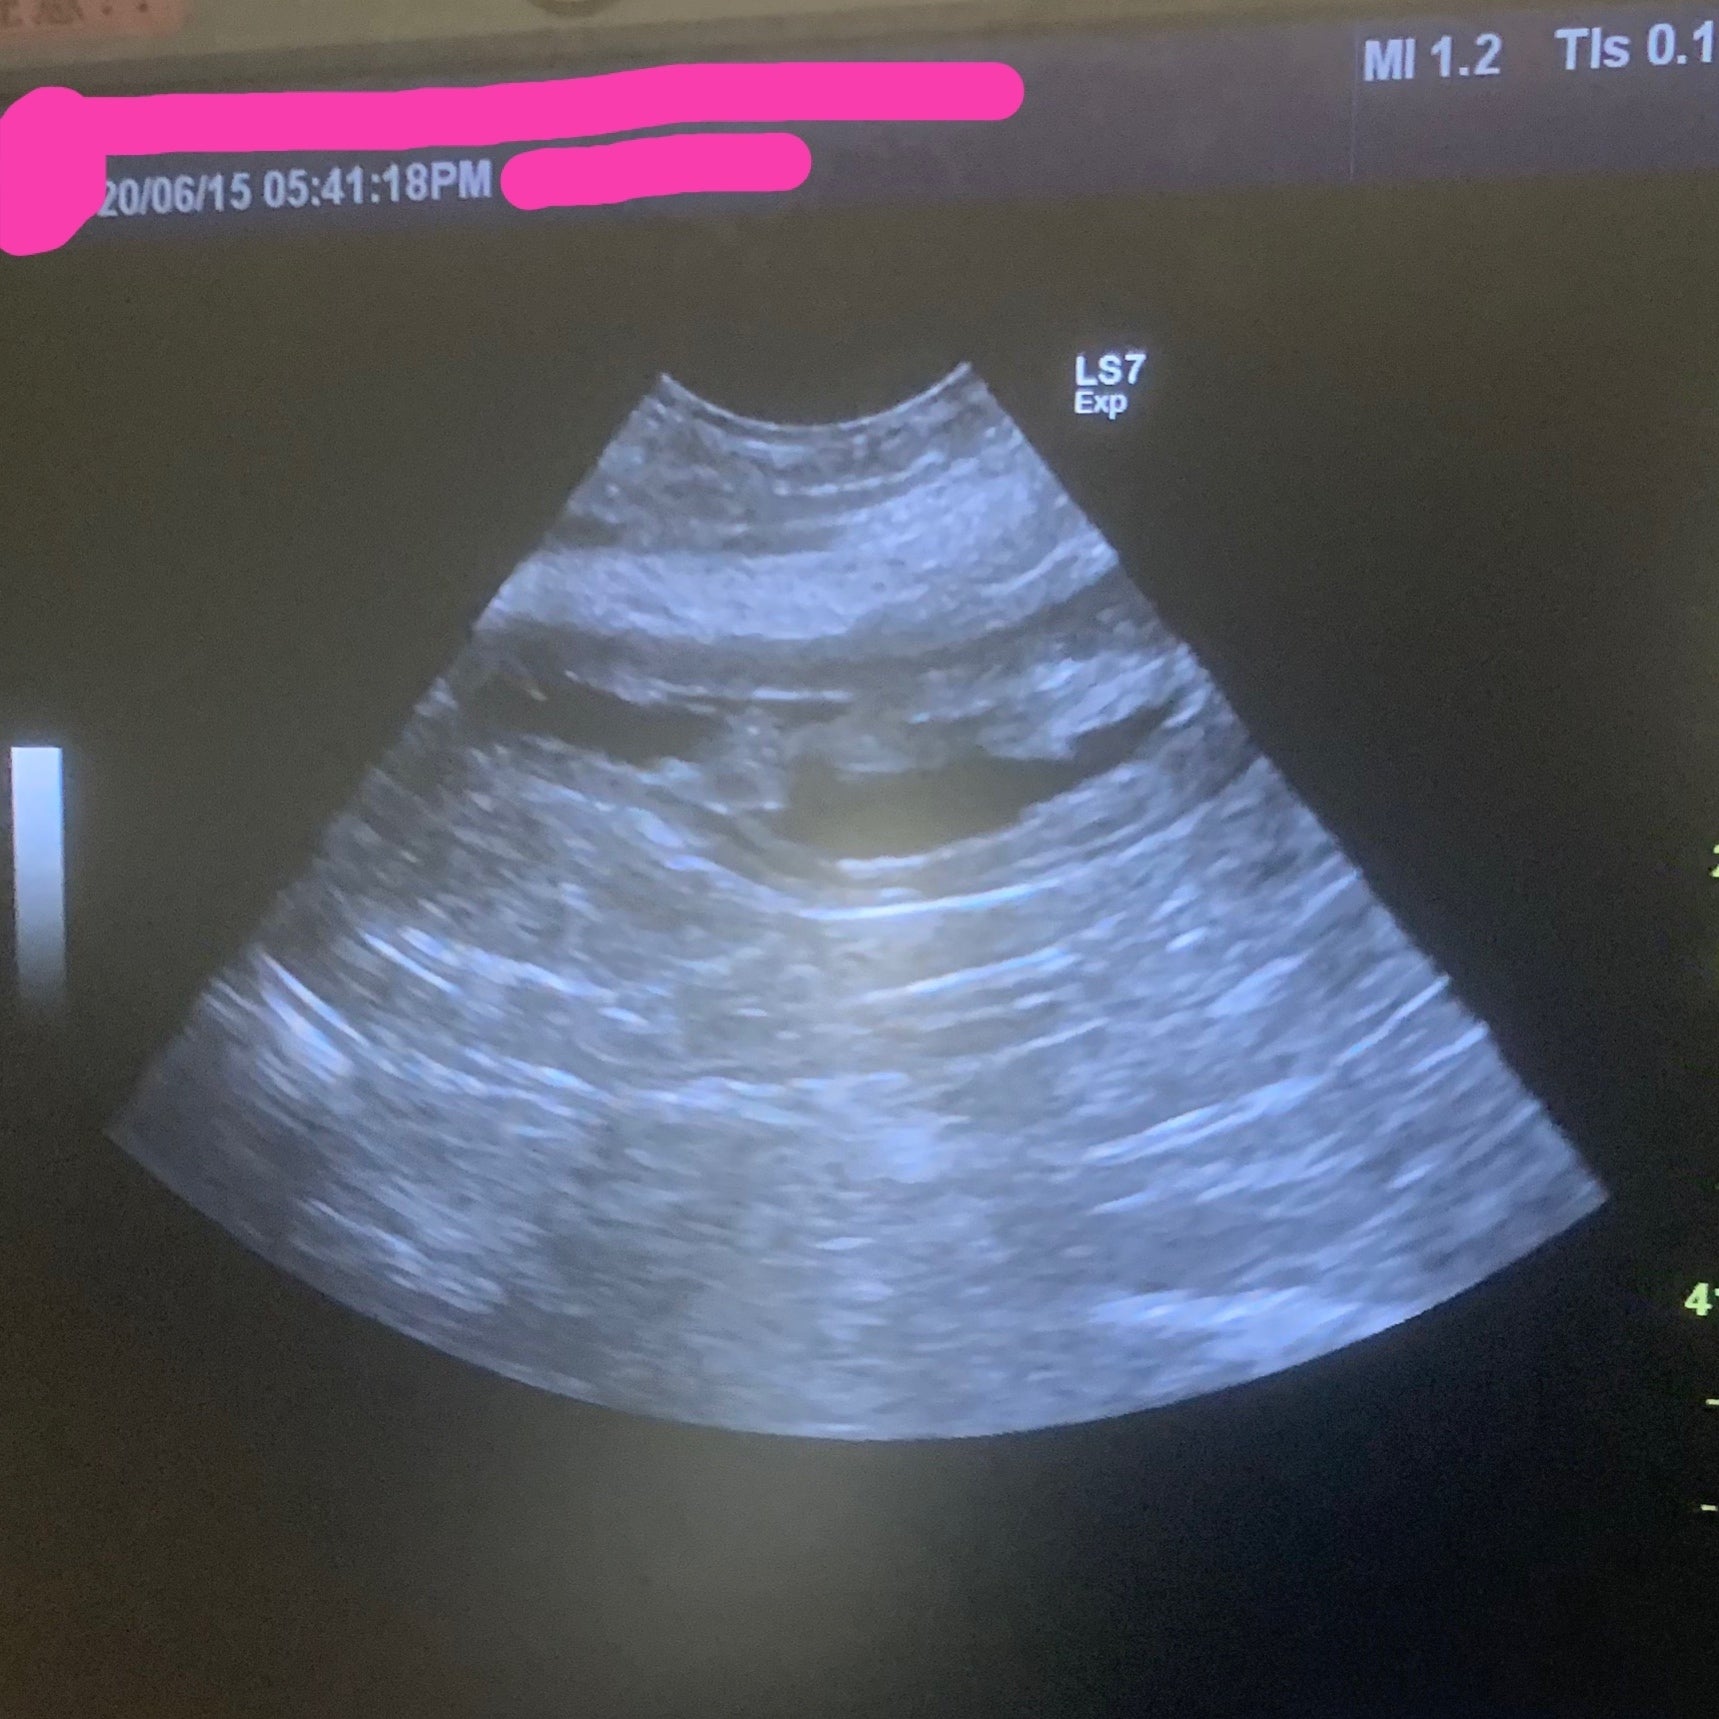

【6月15日】

鼻腔・尿路部洗浄、エコー検査。

尿路部付近の毛刈り。

膀胱内のもやもやは消えていない。

(そんなに早く消えないみたいです)

経過観察。